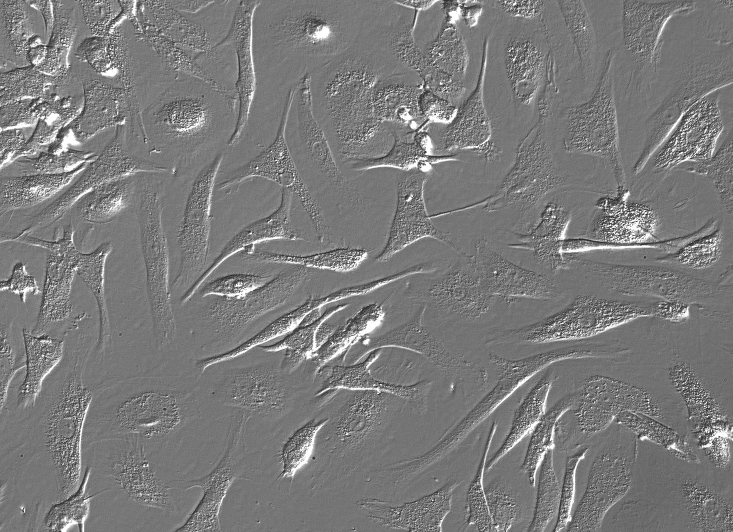

产品名称:HM;人小神经胶质细胞(原代细胞)

来自ScienCell研究实验室的HM从人脑中分离出来。HM在纯化后冷冻保存并冷冻。每个小瓶含有> 1×10 6个细胞,1ml体积。HM的特征在于具有针对CD11b和F4 / 80的抗体的免疫荧光。HM对HIV-1,HBV,HCV,支原体,细菌,酵母和真菌均为阴性。HM保证在ScienCell研究实验室提供的条件下进一步培养; ^ h H但是,HM不建议,因为细胞膨胀或长期培养的常规培养不繁殖。

小胶质细胞是中枢神经系统(CNS)中的神经胶质细胞类型之一,是神经胶质细胞网络的重要组成部分[1]。它们存在于从发育早期到成熟状态的脑实质中。小胶质细胞在脑免疫监视中发挥重要作用。它们可以将MHC II类表达的分子背景中的抗原呈递给CD-4阳性T细胞,并且能够进行Fc介导的吞噬作用,并与造血和组织巨噬细胞共享许多常见抗原[2]。激活后,当脑发育期间或CNS受损时发生程序性细胞死亡时,它们充当脑巨噬细胞以清除组织碎片,受损细胞或微生物。此外,

胶质祖细胞,其根据培养基在体外发育成星形胶质细胞或少突胶质细胞